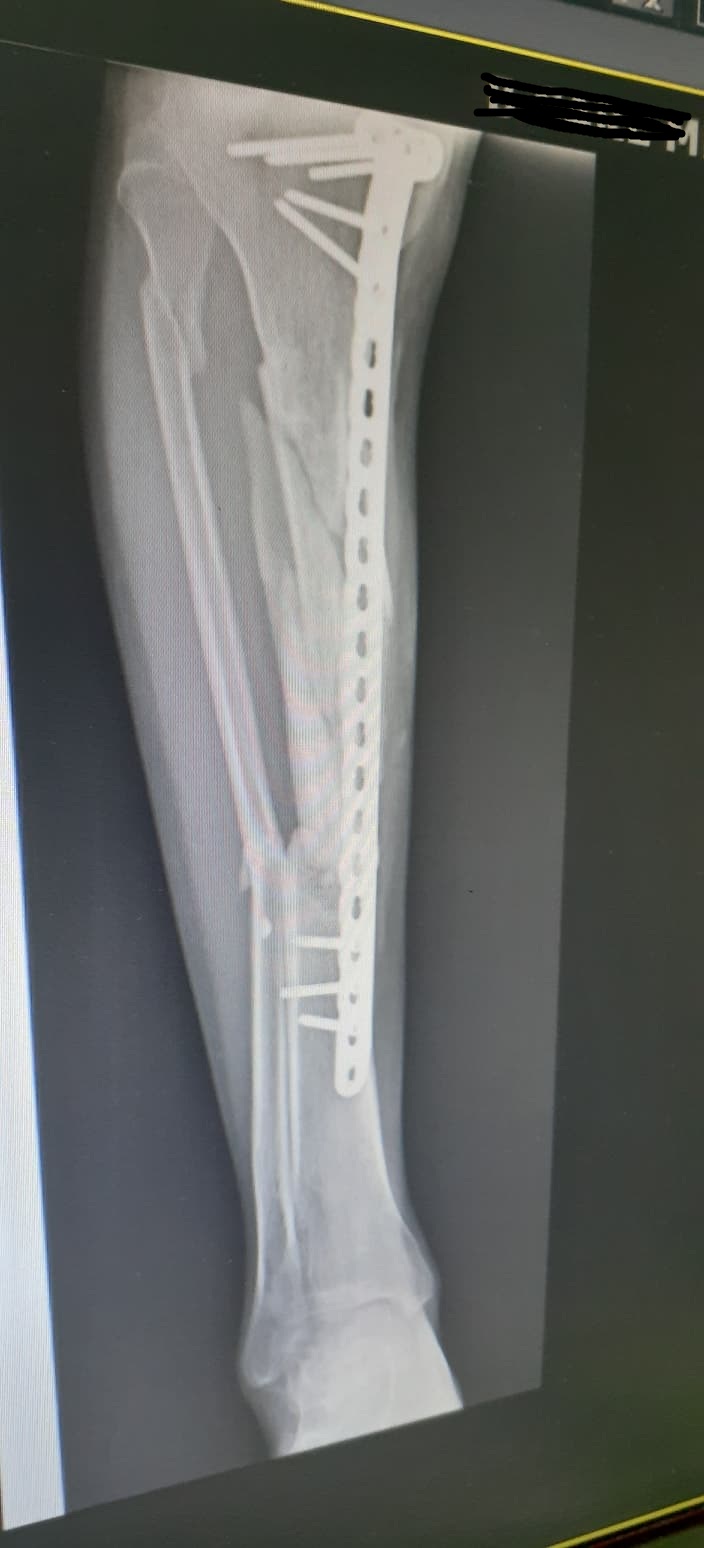

จากภาพเอกซเรย์ที่ปรากฏ หลังจากผ่าตัดมาแล้ว10เดือนครับ คุณหมอให้ลงน้ำหนักได้บ้างโดยการใช้ไม้ค้ำยันเป็นตัวช่วยพยุง แต่แกบอกว่าถ้ามีอาการเสียวให้หยุดเดิน1-2อาทิตย์ตรงนี้หมายความว่าผมสามารถเดินแบบลงน้ำหนักได้ตลอดใช่ไหมครับ (อาการเวลาเดินค่อนข้างจะเจ็บช่วงน่องขามาก)

ภาพข้างล่างหลังจากผ่าตัด4เดือน